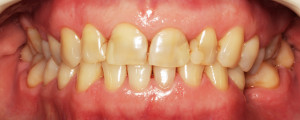

Do kliniki Stomatologia Bez Bólu zgłosiła się pacjentka, lat 61 z problemem nadwrażliwości zębów. Po przeprowadzonym wywiadzie stwierdzono spożywanie sporej ilości sezonowych owoców (truskawki, wiśnie, czereśnie, czarna porzeczka), nawet 3 razy dziennie. Następnie wykonano badanie wewnątrzustne. Stwierdzono obecność płytki nazębnej, ciemnego osadu oraz kamienia nazębnego na części trzonowców:

Wykonano higienizację jamy ustnej poprzez usunięcie kamienia nazębnego skalerem ultradżwiękowym, zdjęciem osadu i płytki nazębnej poprzez piaskowanie air flow plus oraz classic, a następnie wypolerowaniu gumką ze specjalistyczną pastą polerską: